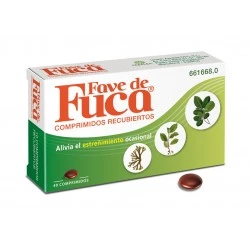

¿Sufres de estreñimiento? Encuentra alivio con Dulcolaxo Bisacodilo 5mg (30 comprimidos), Agiolax en 250g y Plantaben 3,5g (30 sobres). Estas pastillas, remedios y medicamentos libres de receta, son opciones efectivas para tratar el estreñimiento. ¡Prueba ahora!